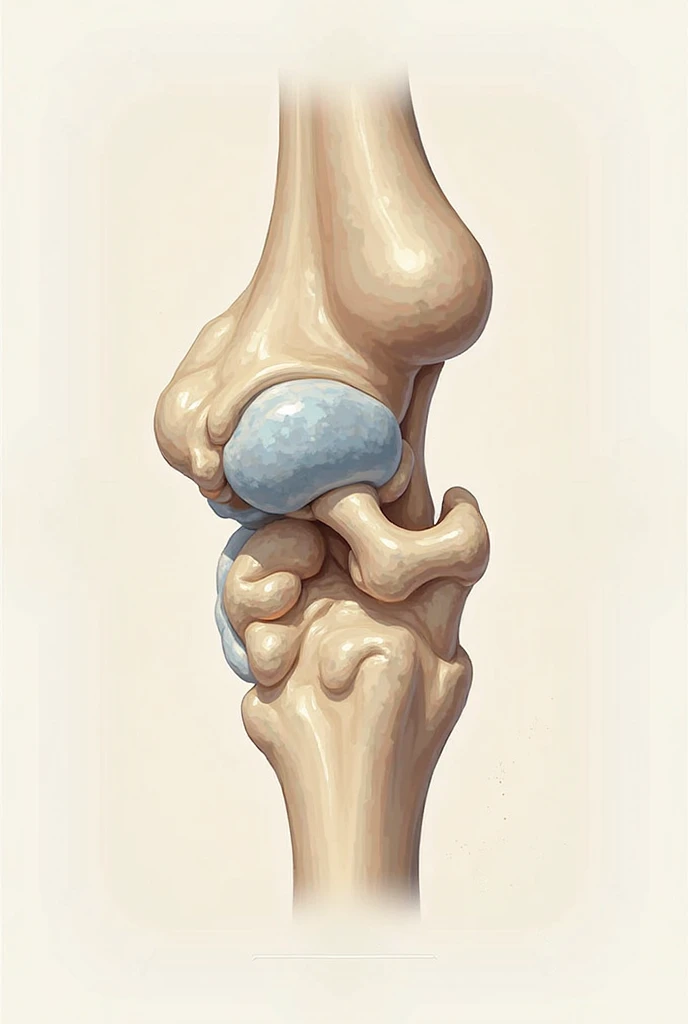

Close-up of human knee,There is a bone in the middle, knee, Knees, surreal bone structure, Protruding bones, Realphotos, orthographic view, Look across the shoulder, medical depiction, Osteoarticular joints, computer generated, hyper realisitc, sharp bone structure, joint, digital painted

Close-up of human knee

There is a bone in the middle

knee

Knees

surreal bone structure

Protruding bones